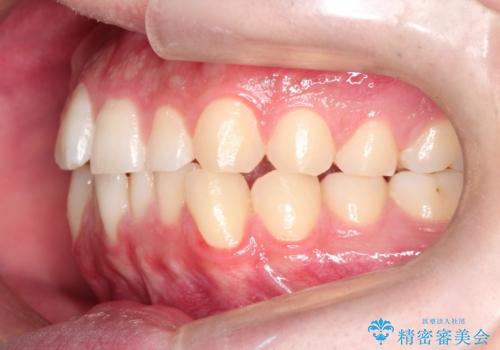

- 前歯の歯並びの改善を希望され来院された患者様です。

初診時の歯並びの状態としては、上下ともに前歯部の中等度以上のがたつき(叢生)があり、右の前歯が1本飛び出した状態でした。

抜歯は行わず上下顎ともに、主に歯列弓の拡大とディスキング(歯と歯の間に隙間を作る処置)を行い叢生を改善しました。